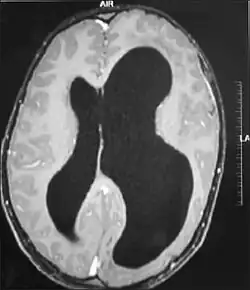

| MRI images showing megalencephaly in four family members who all have unusually large skulls (the family is affected by an autosomal recessive syndrome caused by a KIF7 mutation that induces multiple epiphyseal dysplasia)[1] | |

A mutation in the PI3K-AKT pathway is believed to be the primary cause of brain proliferation and ultimately the root cause of megalencephaly. This mutation has produced a classification of brain overdevelopment that consists of two syndromes including megalencephaly-capillary malformation (MCAP) and megalencephaly-polydactyly-polymicrogyria-hydrocephalus (MPPH).[4] Megalencephaly is usually diagnosed at birth and is confirmed with an MRI.

A neurological exam will then be performed using the technology of an MRI machine in order to confirm the diagnosis of megalencephaly. These imaging tests give detailed information regarding brain size, volume asymmetry and other irregular developments linked with MCAP, MPPH and hemimegalencephaly.[2][21]